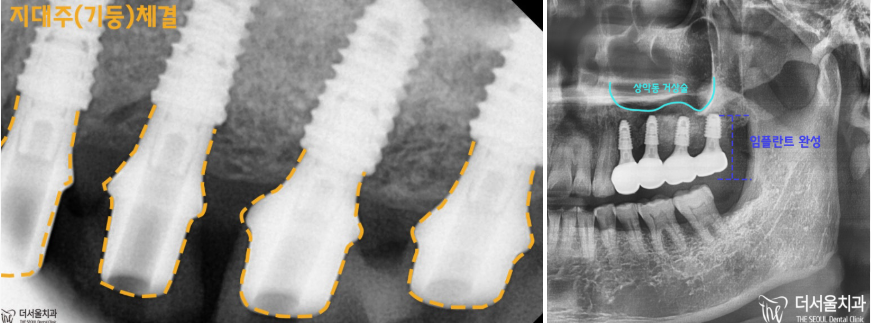

이제 드디어,

치료 결과를 보여드리도록 하겠습니다.

픽스쳐 위에

어버트먼트=지대주를 체결하고

임플란트 보철을 붙여드릴 수 있었습니다.